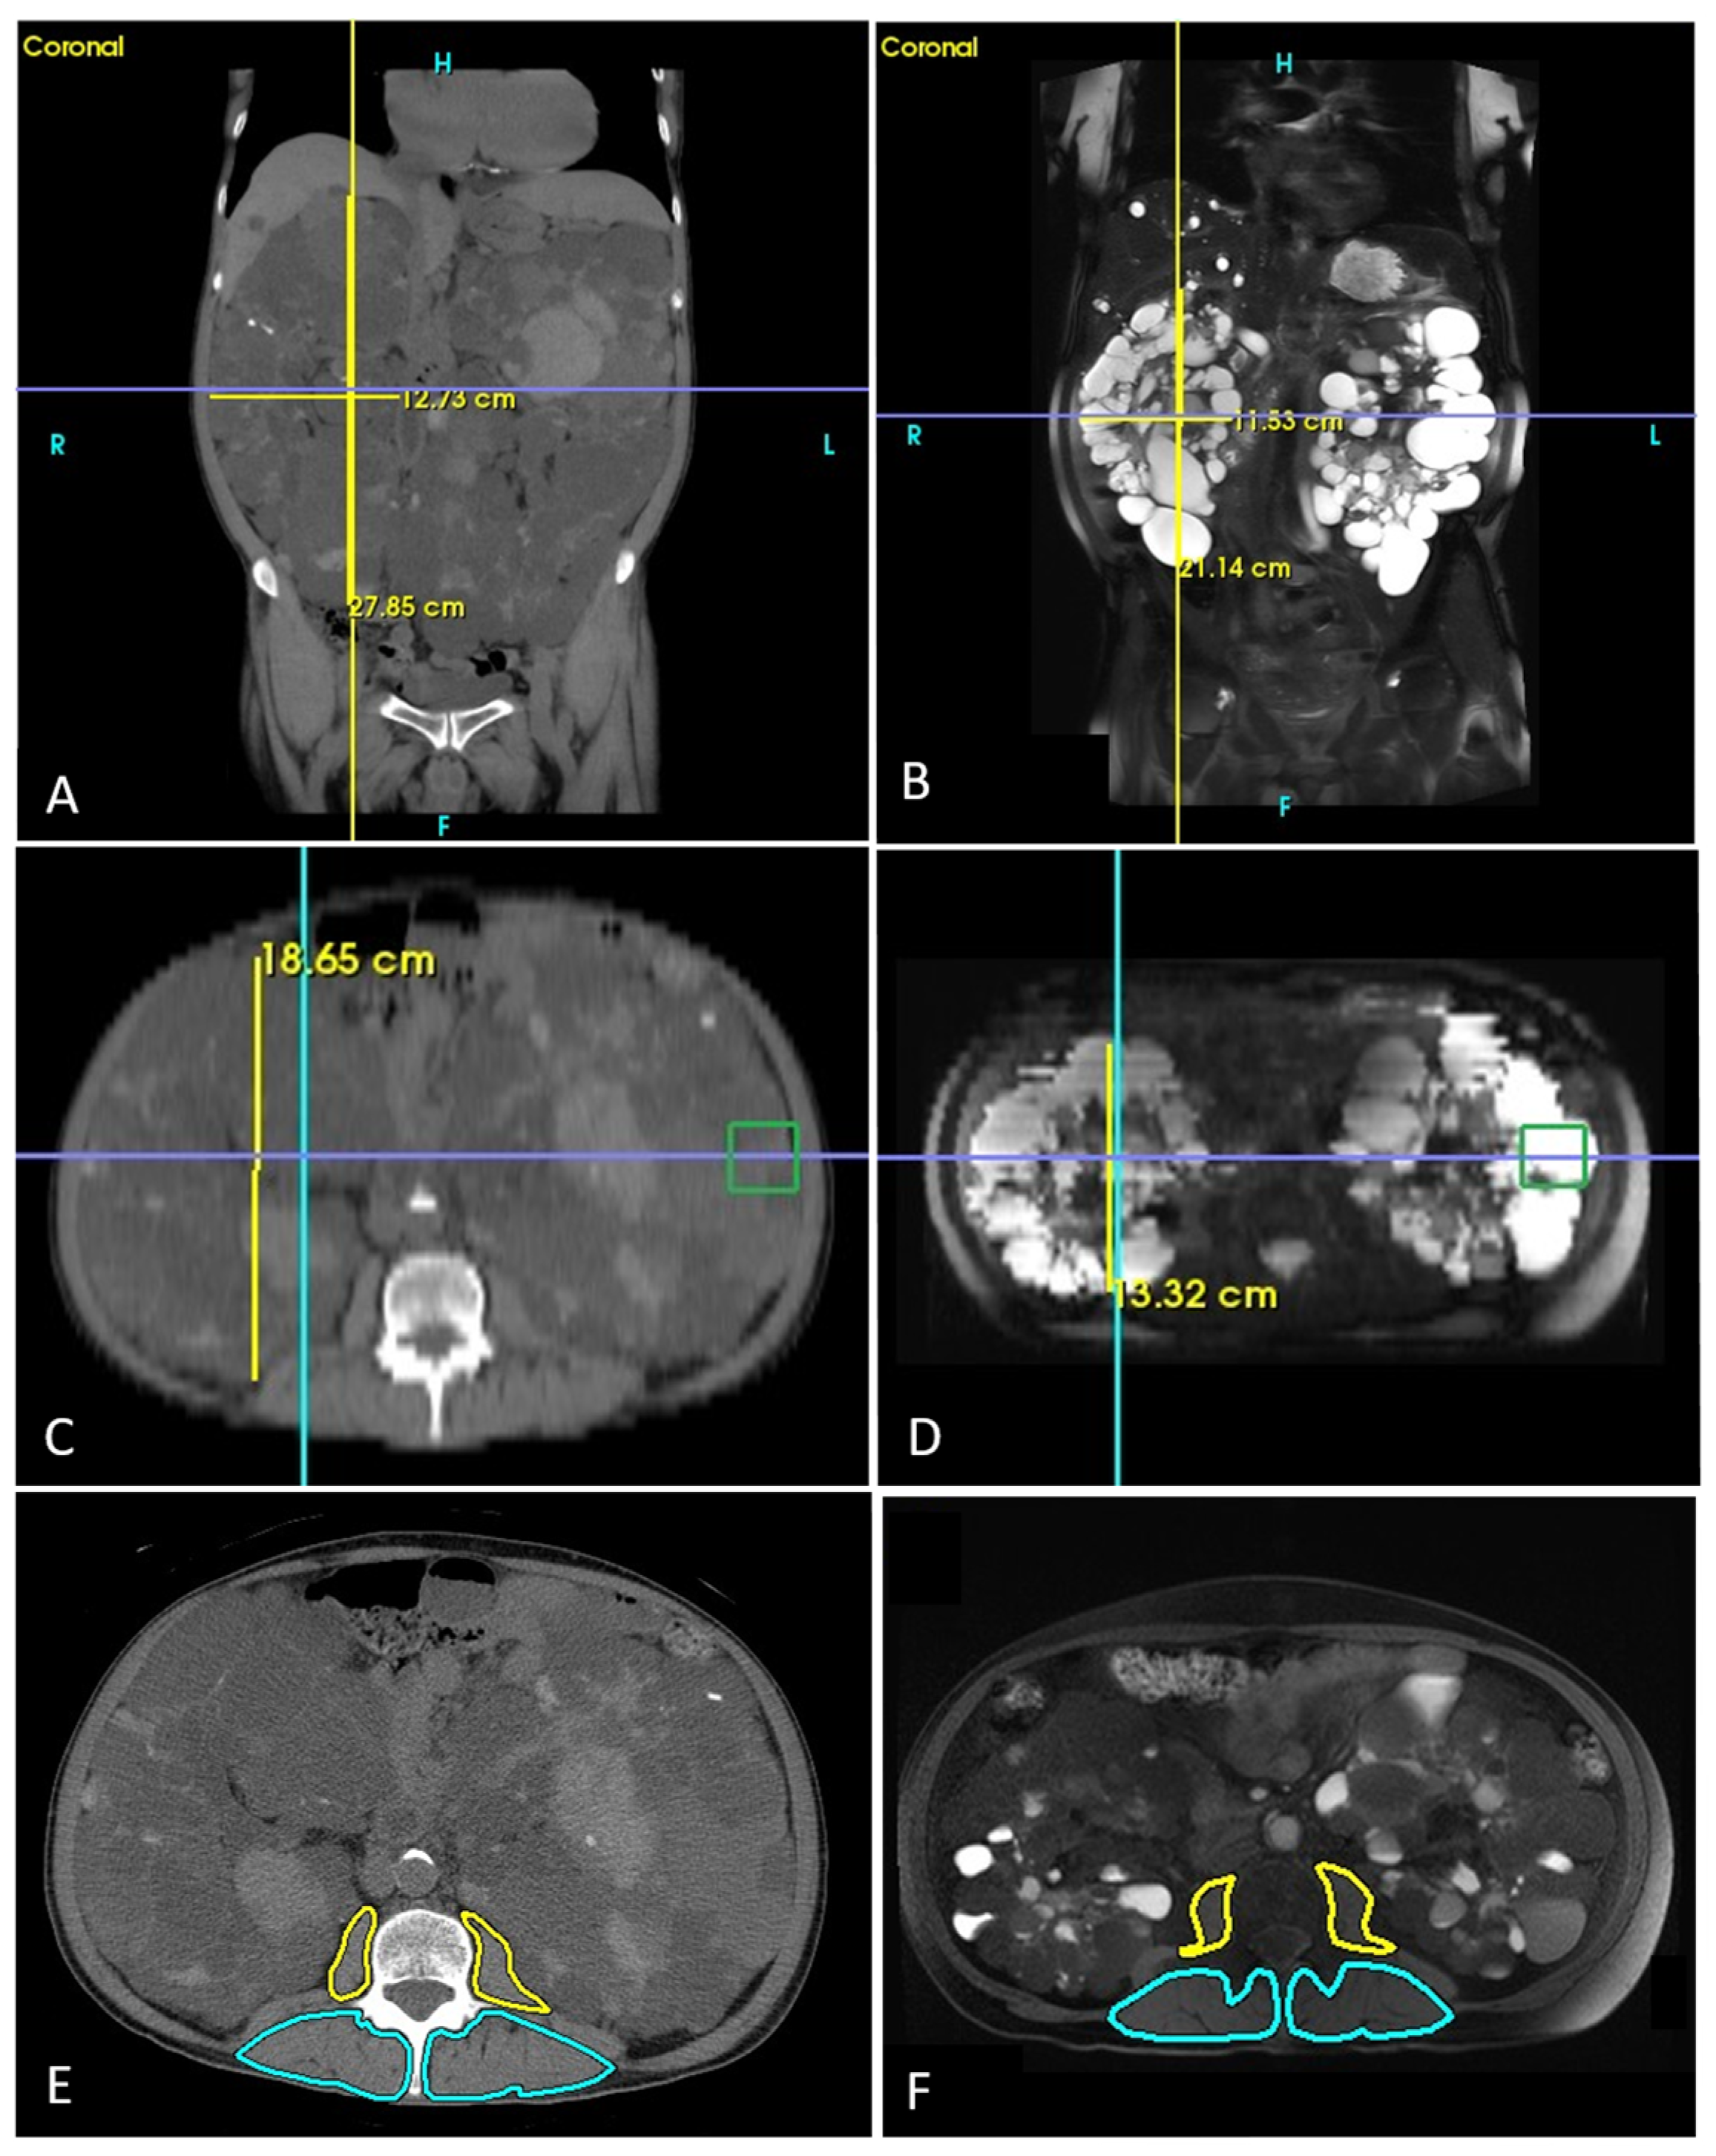

2.2. Study Variables and Imaging Acquisition

2.3. Imaging Processing